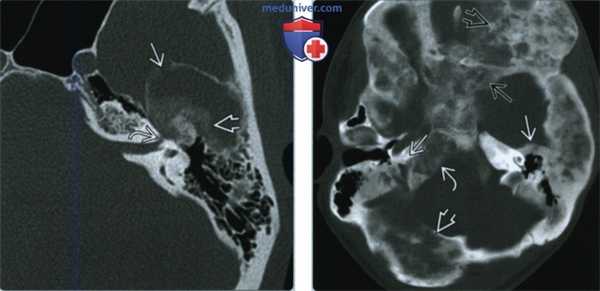

(Слева) При аксиальной КТ в передних отделах левой височной кости определяются очаги кистозной ФД, выглядящие агрессивными. Определяется также нежное «матовое стекло». Обратите внимание на визуализирующийся лабиринтный сегмент канала лицевого нерва и поражение ямки коленчатого ганглия.

(Справа) При аксиальной КТ в костном окне определяется полиостотическая фиброзная дисплазия с поражением обеих височных костей. Хорошо видны другие множеавенные очаги, в т.ч. в затылочной кости справа, в скате, клиновидной и лобной кости.